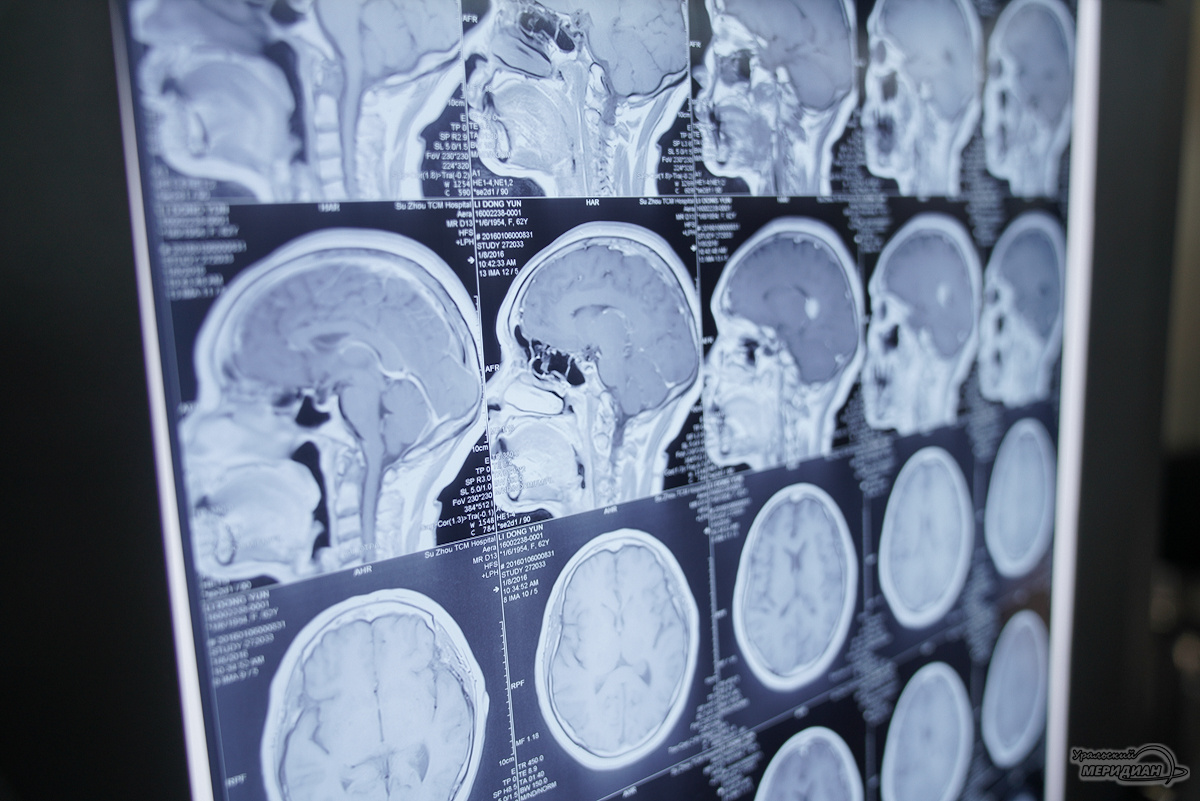

Мойя-Мойя (с японского переводится, как «клубы дыма») – заболевание, при котором из-за сужения и закупорки крупных артерий головного мозга возникает сеть мелких сосудов, напоминающих дым на ангиограмме. Патология приводит к ухудшению кровоснабжения мозга.

Под руководством нейрохирурга Тимура Гасанова медицинская бригада, включающая реаниматолога Дениса Семенчука, анестезистку Венеру Ничипоренко и медсестру Альфию Нуруллину, провела первую сложную операцию. В ходе вмешательства через небольшой разрез в височной области была выделена поверхностная височная артерия и с помощью микроскопа и тончайших швов специалисты создали шунт, обеспечив кровоток в обход закупорки.